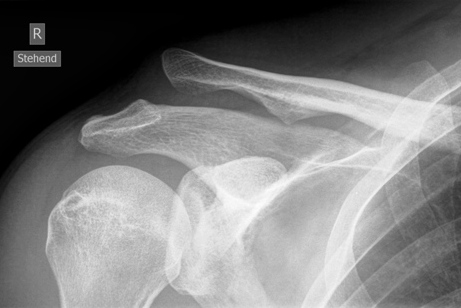

AC Luxation Typ Rockwood 3 vor Versorgung mit Balser Hakenplatte (Clavicular Hook Plate)